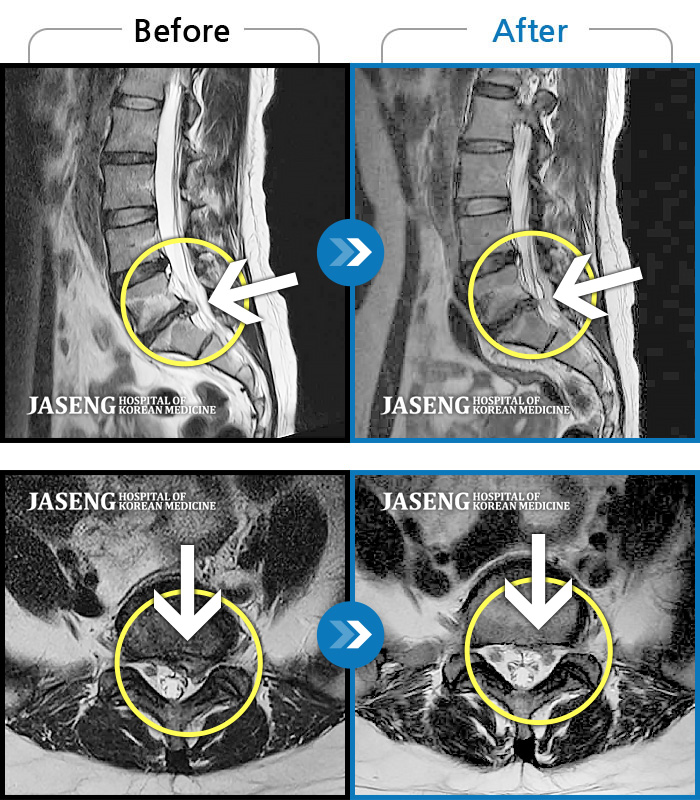

MRI ġ

88 MRI ũ ʸ Ȯϼ.